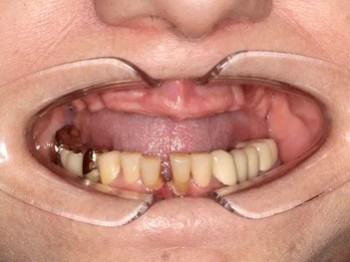

21 работа в портфолио